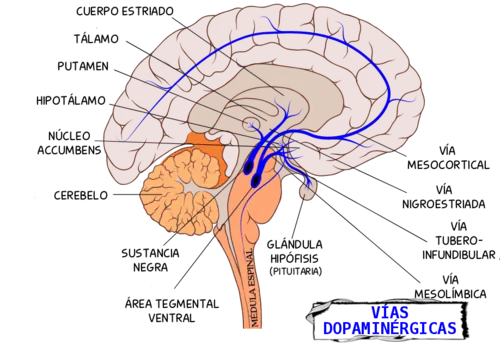

Existen diferentes sustancias que actúan como neurotransmisores, algunas de las más importantes son las siguientes: GABA, acrónimo de ácido g-aminobutírico, serotonina, acetilcolina, dopamina, noradrenalina y endorfina. Las vías dopaminérgicas, por ejemplo, son rutas de neuronas que funcionan con la dopamina como neurotransmisor. Estas vías son de gran interés en la función del cerebro y se ha comprobado que su alteración puede provocar diferentes enfermedades, entre ellas la enfermedad de Parkinson.[17][18]

Los ganglios basales en realidad deberían llamarse núcleos basales pues no son verdaderos ganglios. Son un conjunto de estructuras cerebrales formadas por sustancia gris que están situados debajo de la corteza y desempeñan importantes funciones, una de las principales es el control de los movimientos voluntarios, pero también intervienen en el procesamiento de la información sensorial y en aspectos relacionados con la memoria y las emociones. Están conectados con la corteza cerebral y funcionan con un alto grado de integración. Pueden diferenciarse los siguientes:[29]

- Cuerpo estriado, formado por el núcleo caudado, el putamen y el núcleo accumbens.

- Sustancia negra